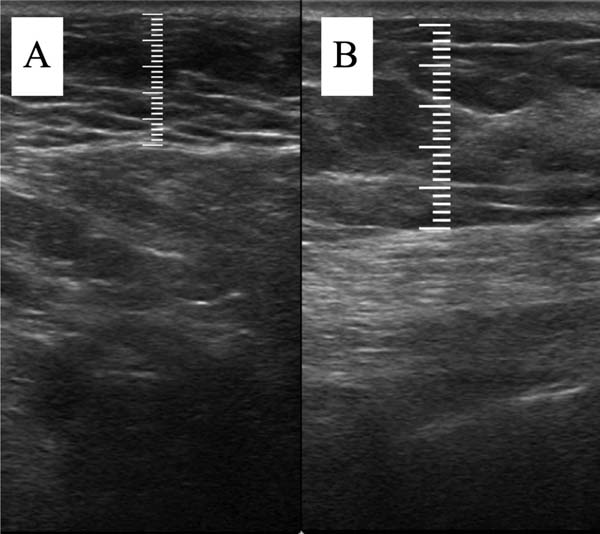

A mensuração da espessura do tecido subcutâneo é realizada de forma vertical, do ponto mais alto (logo na transição da epiderme) ao ponto mais baixo (na transição com o tecido muscular) da espessura de tecido subcutâneo. Essa medida é de fácil reprodutibilidade para quem possui aptidões básicas em ultrassonografia. ►Fig. 2. A medida da espessura de tecido subcutaneo na mama lipoenxertada foi realizada no pré- e pós-operatório imediato da lipoenxertia, e após 15,30, 90 e 180 dias. As medidas foram feitas atraves da ultrassonografia, em milimetros, medindo a distancia vertical do ponto mais superior (proximo à epiderme) ao mais inferior (proximo à musculatura adjacente) do tecido subcuta neo no ponto previamente definido. Foi utilizado equipamento de ultrassom modelo GE, LOGIQP6 (GE Healthcare) com uso de sonda linear de 11L com faixa de frequencia de 12 a 6 MHz, operado por cirurgião com pós graduação lato sensu em ultrassonografia geral. ►Fig. 3.

Fig. 2 - Ponto de mensuração ultrassonográfica em tecido subcutâneo. (A) Pré-operatório. (B) Pós-operatório.